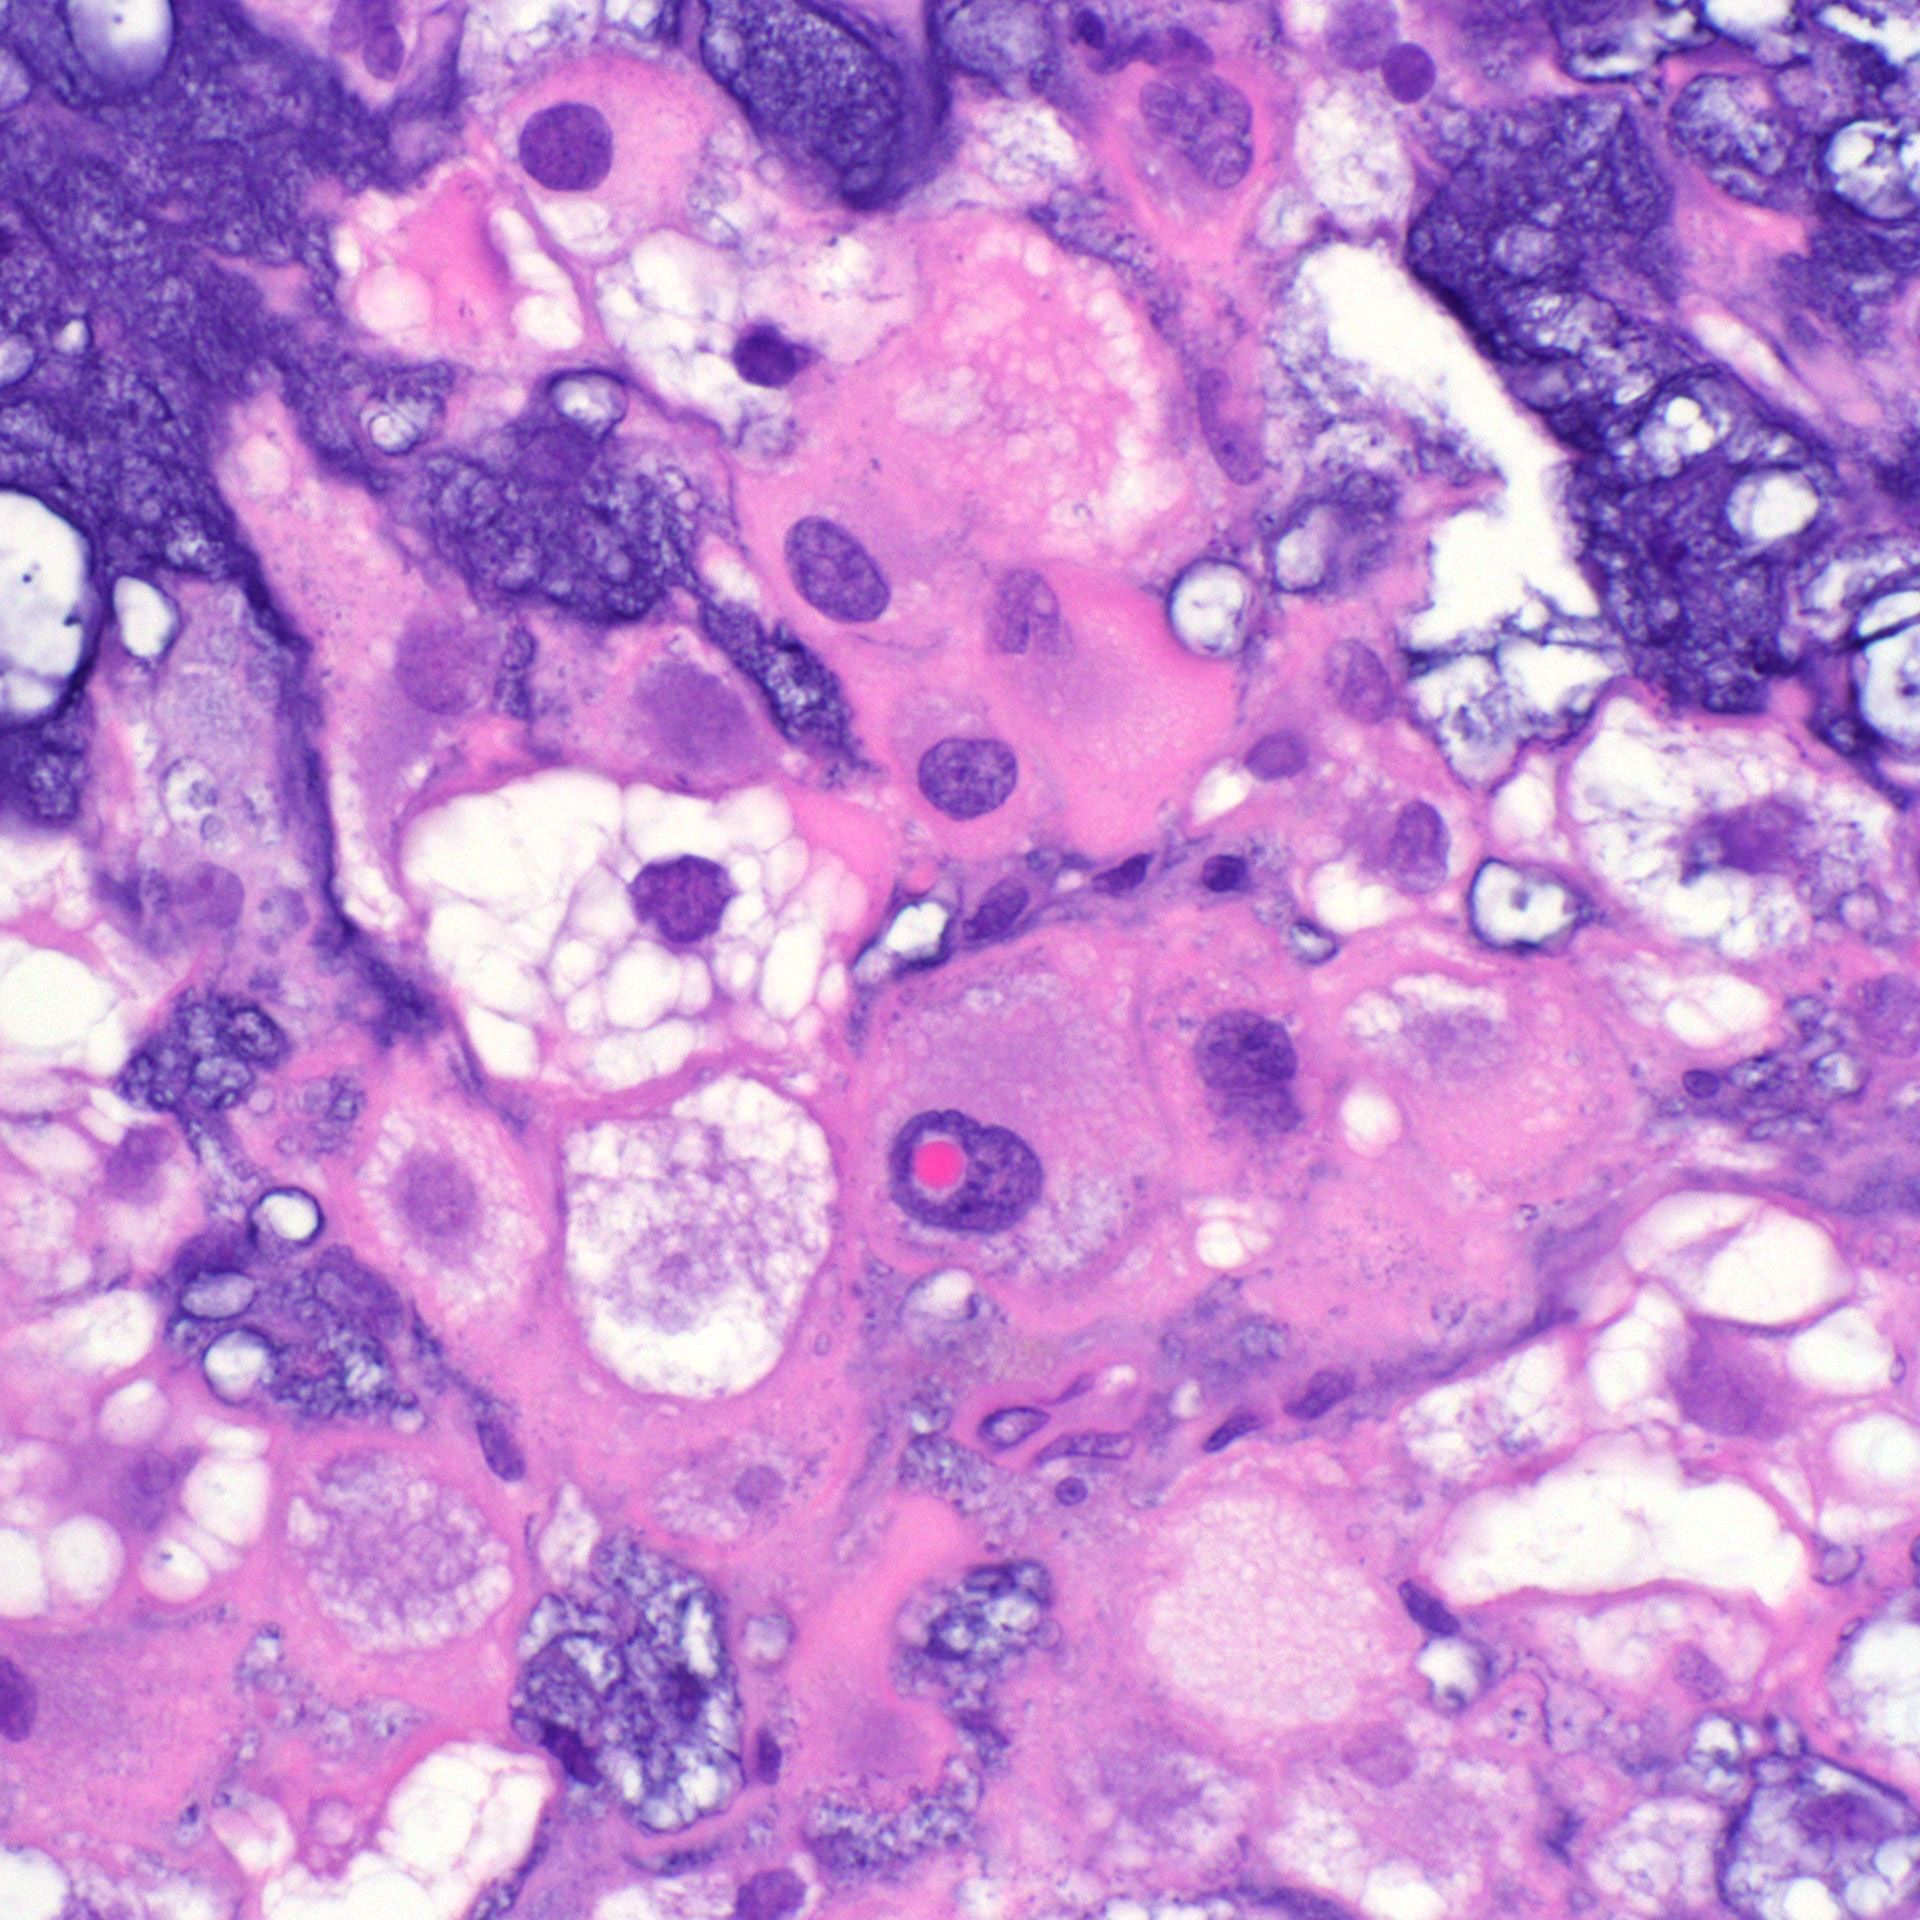

What process is happening here? How old is this patient?

Answers & pics w labels: kikoxp.com/posts/20899